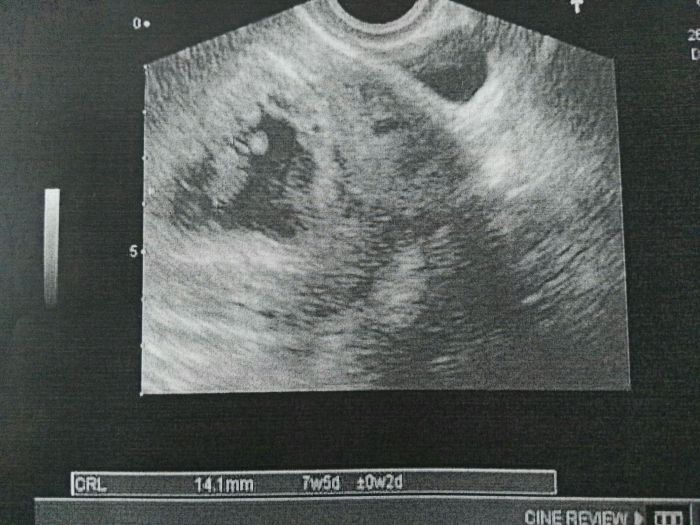

Maci: Tak mám první fotečku ze středy :) vše je prý ok a odpovídá, jen večer jsem opět začla trochu krvácet a byla v tom i sražená krev... nicméně vše bez bolesti a po předchozích zkušenostech vím, že se mi stávalo a bylo to ok, jen prostě tělo vypudí to, co tam být nemá. Kafe si dávám tak 1x za dva dny a jen jedno, ani není taková chut.

Janyys jojo srdíčko už bylo krásné vidět jen tam překážel ještě zbytek váčku. Ale už bude za chvilku 20.7 tak snad budu mít lepší fotečku :) i když moje dr je taková že utz dělá sem tam asi jak se jí zachce. Kolikrat sem se u kluků divila že utz nic na křesle mě prohmátla a za 5 min sem byla venku. Na hodinové čekání v čekárně dobrý